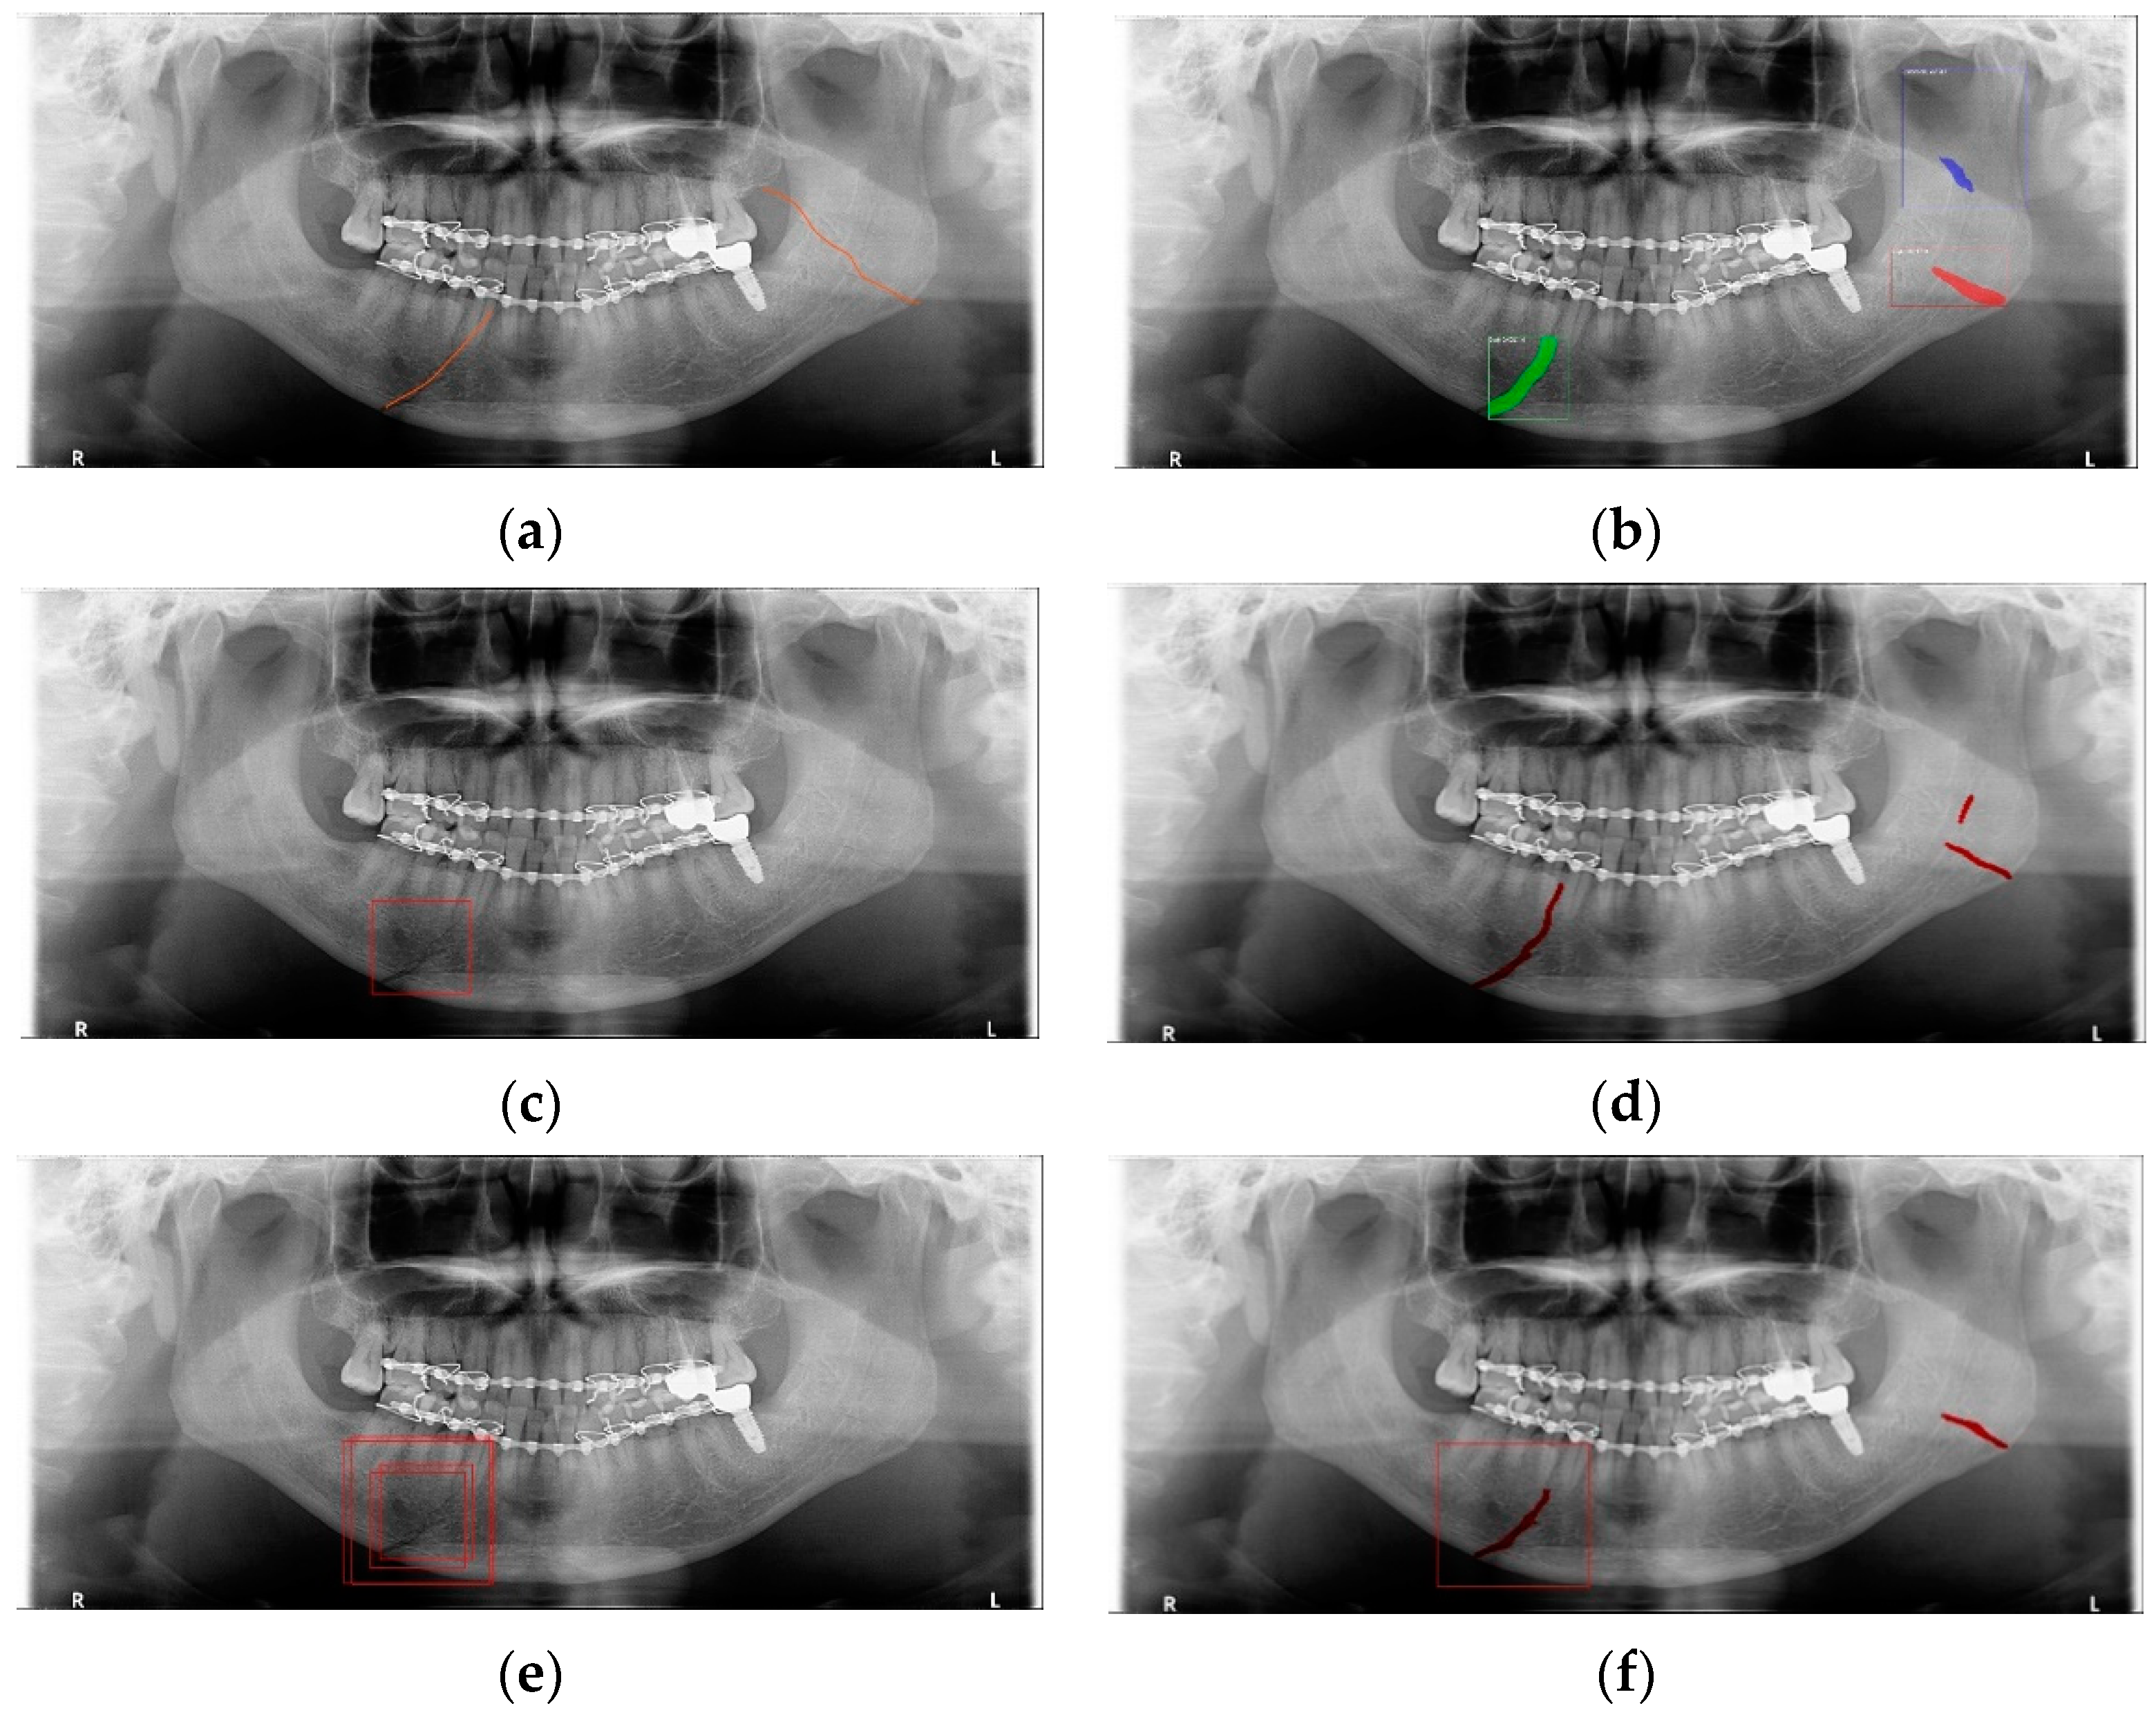

In Table 6, the parameters used for training are indicated, and in Figure 11, Figure 12 and Figure 13, the results of the doctor’s diagnosis, Mask R-CNN, YOLOv4, U-Net, LAT YOLOv4, and U-Net withYOLOv4 are compared. Figure 11 illustrates fractures in the angle and condylar regions, and in Mask R-CNN, the symphysis is misdiagnosed as a fracture. In Figure 12, the Mask R-CNN misdiagnoses the symphysis as a fracture, the result of the fact that the YOLOv4 module has better performance detecting angle fractures rather than does the LAT YOLOv4, as shown in Figure 12c,e. In short, the LAT-processed image does not always have the advantage of better revealing fractures compared with the normal panoramic radiograph.

Figure 13.

The comparison of mandibular fracture detection: (a) oral and maxillofacial radiologist, (b) Mask R-CNN (with colored polygons and boxes), (c) YOLOv4 (with a red box), (d) U-Net (with red lines), (e) LAT YOLOv4 (with red boxes), and (f) U-Net with LAT YOLOv4 (with a red box and lines).

In Figure 13, the ramus is misdiagnosed as a fracture. Therefore, Mask R-CNN had the lowest precision score because the misdiagnosis rate was higher than that of the other modules (Figure 16). The YOLO module has a low misdiagnosis rate, while the ‘undiagnosis’ rate is high; therefore, the F1 score is low owing to the ’undiagnosis’ rate. As shown in Figure 11, Figure 12 and Figure 13, YOLOv4 and LAT YOLOv4 have strong advantages over location information; therefore, they tend to detect well in the condyle region, that is, the side fracture, while they tend to detect poorly in the symphysis, body, and angle regions, where location information is ambiguous. Unlike Mask R-CNN and YOLO, U-Net is an image segmentation deep learning network, not an object detection deep learning network and labels mandibular fractures. U-Net marks fractures as lines on the label during training; however, it is difficult to label dislocated fractures, such as condyle fractures (Figure 11). Therefore, in the U-Net module, the side fracture was not diagnosed or misdiagnosed, and the precision-recall score was lower than that of the YOLO modules. It was judged that if the two deep learning networks are used together, the shortcomings of YOLO and U-Net complement each other and help improve mandibular fracture performance. In the proposed module, duplicate boxes that occurred in LAT YOLOv4 were removed before merging with the U-Net. In the proposed U-Net with LAT YOLOv4, the precision score was reduced; however, many ‘undiagnoses’ were eliminated; therefore, the recall score was increased, and it can be observed that the overall F1 score improved the performance by more than 90%.

Deep learning networks such as Mask R-CNN, YOLOv4, and U-Net have been used to detect mandibular fractures using only panoramic images. The advantages of the three networks can be identified experimentally through panoramic mandibular fracture images. First, Mask R-CNN specifically marks the fracture area; however, it also marks fractures in areas that are not fractured, such as dark shaded areas in the panoramic image or gaps between teeth; therefore, the false diagnosis rate is higher than that in other deep learning networks. In YOLO, the location information for the six classes divided into anatomical structures is helpful to detect mandibular fractures. However, there are some undiagnosed fracture areas, other than the fractures of the condyle and coronoid process with clear characteristics and location. Unlike the above two deep learning networks, U-Net performs training by labeling fracture and panoramic images. When creating training fracture labeling data, the dislocated fracture area of the condyle fracture is difficult to label. Unlike YOLO, the side fracture area is weak, causing an increase in the misdiagnosis rate when learning by labeling a dislocated fracture. In Figure 17, the mandibular fracture detection results images of LAT YOLOv4 and U-Net with LAT YOLOv4 are compared. The panoramic images in the first and second rows demonstrate the advantages of YOLO and U-Net. While YOLO detects condyle dislocation fractures well, it does not detect angle fractures; however, U-Net detects angle fractures well. The panoramic images in the third and fourth rows show that the undiagnosed area is reduced by using U-Net for the angle area that the LAT YOLOv4 module does not diagnose. Because U-Net performs semantic segmentation, it is advantageous for the segmentation of fractures spread over a wide area. Consequently, the undiagnosed case in the middle of the mandible, where LAT YOLOv4 is weak, is somewhat supplemented by the U-Net module.

Figure 17.

The comparison of LAT YOLOv4 and U-Net with LAT YOLOv4 detection results. (a) LAT YOLOv4 (with red boxes), and (b) U-Net & LAT YOLOv4 (with red boxes and lines).